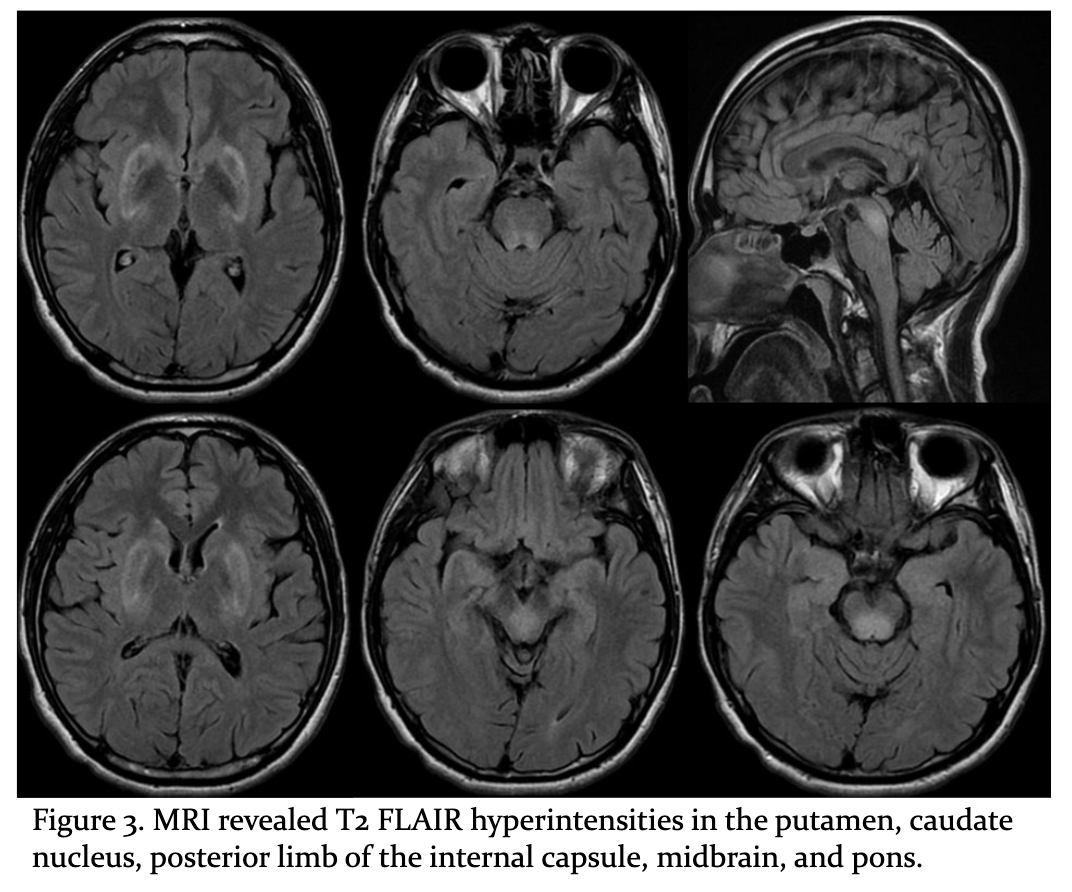

Results: A 24-year-old male, without prior systemic disease, contracted COVID-19 in June 2022. Within few days, he presented with excessive drooling, mild slurred speech, asymmetric facial expressions, and mild fluctuating right limb incoordination and clumsiness which exaggerated after exercise. In early 2023, he experienced 2 episodes of transient worsening neurological symptoms including: right limbs hemi-dystonia, chorea/ballism, spasmodic dysphonia and swallowing difficulties reported after physical exhaustion and respiratory infections. It was not until April 2023 when his left limbs were also involved that he sought for medical attention. Other neurological examination revealed mild memory and calculation impairment, orofacial dystonia, ataxia and presence of Kayser–Fleischer rings [figure1]. Laboratory results showed decreased ceruloplasmin (3.0 mg/dL), decreased serum copper (38 µg/dL), and elevated free copper (29 µg/dL) and urine copper (235 µg). Surface EMG of both upper limbs showed prolonged MUAP bursts with co-contraction of agonists and antagonists muscles [figure2]. Brain MRI revealed T2 FLAIR hyperintensities in the putamen, caudate nucleus, posterior limb of the internal capsule, midbrain, and pons [figure3]. PCR direct sequencing for ATP7B mutation analysis identified two compound heterozygous mutations (c.2333G>T/p.R778L, c.2975C>T/p.P992L) [figure4]. Treatment with zinc acetate and Trientine stabilized his symptoms.

Figure 3